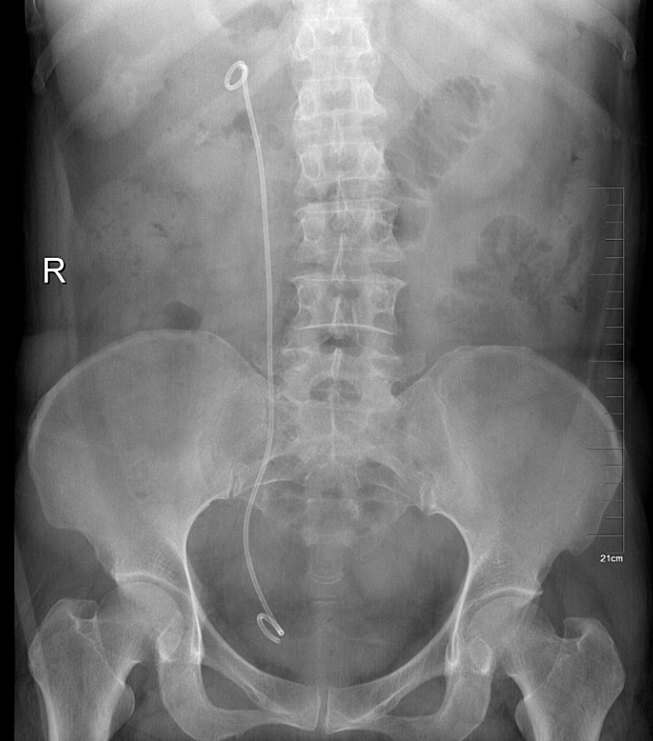

输尿管软(硬)镜碎石取石术后注意事项:

574x423 - 20KB - JPEG